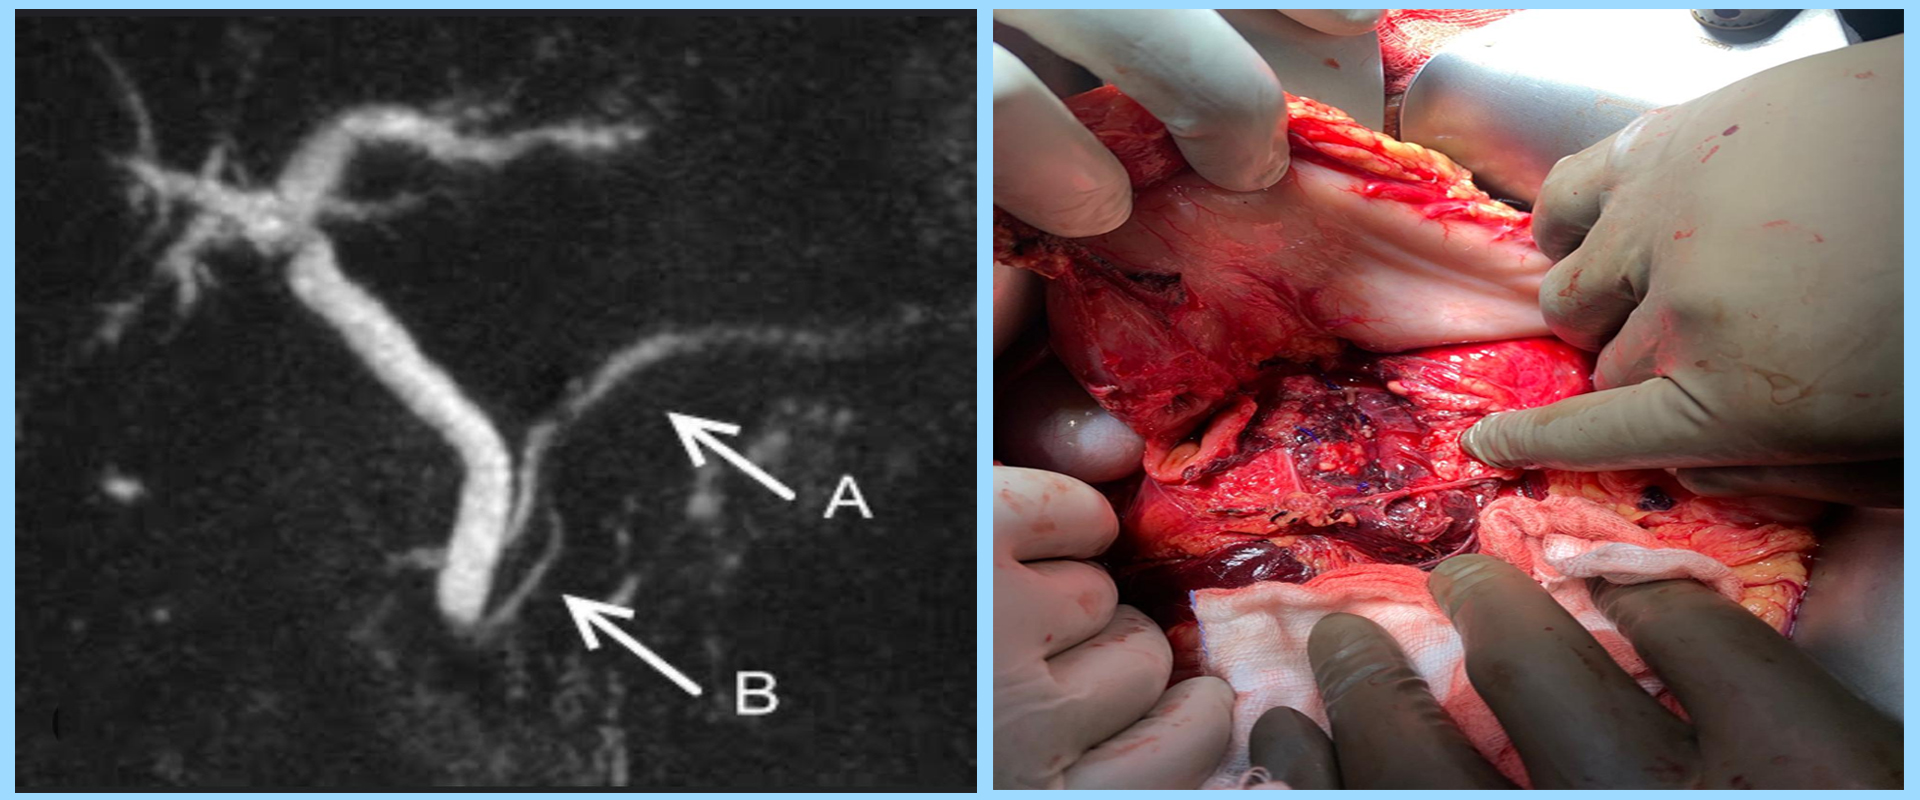

Diagnosis is typically made through imaging studies, such as:

• CT scan

• Surgical intervention for severe injuries